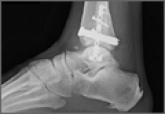

Tibialis Posterior Tendon Entrapment Within Posterior Malleolar Fracture Fragment

Management of posterior malleolus fractures continues to be controversial, with respect to both need for fixation and fixation methods.